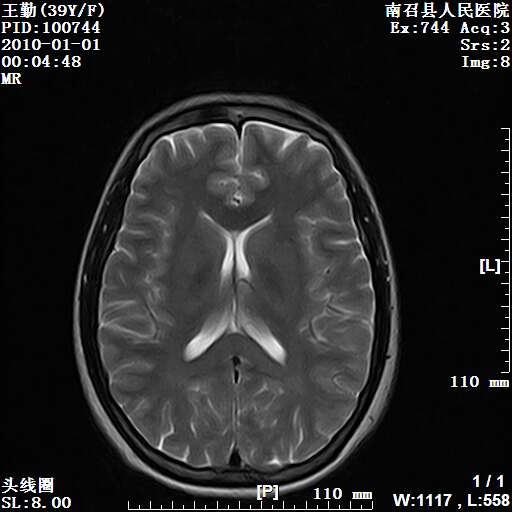

以下是引用随光逐影在2010-1-22 9:03:00的发言:[br]考虑左侧中颅窝(蝶骨翼区)脑膜瘤侵犯蝶骨翼并突入左侧眼眶。

以下是引用水过无痕在2010-1-22 14:55:00的发言:[br]一、定位:颅外占位;二、定性:恶性可能性大;三、组织来源:来源于左侧眼外直肌或其他部位;考虑为:横纹肌肉瘤>转移瘤>脑膜瘤.